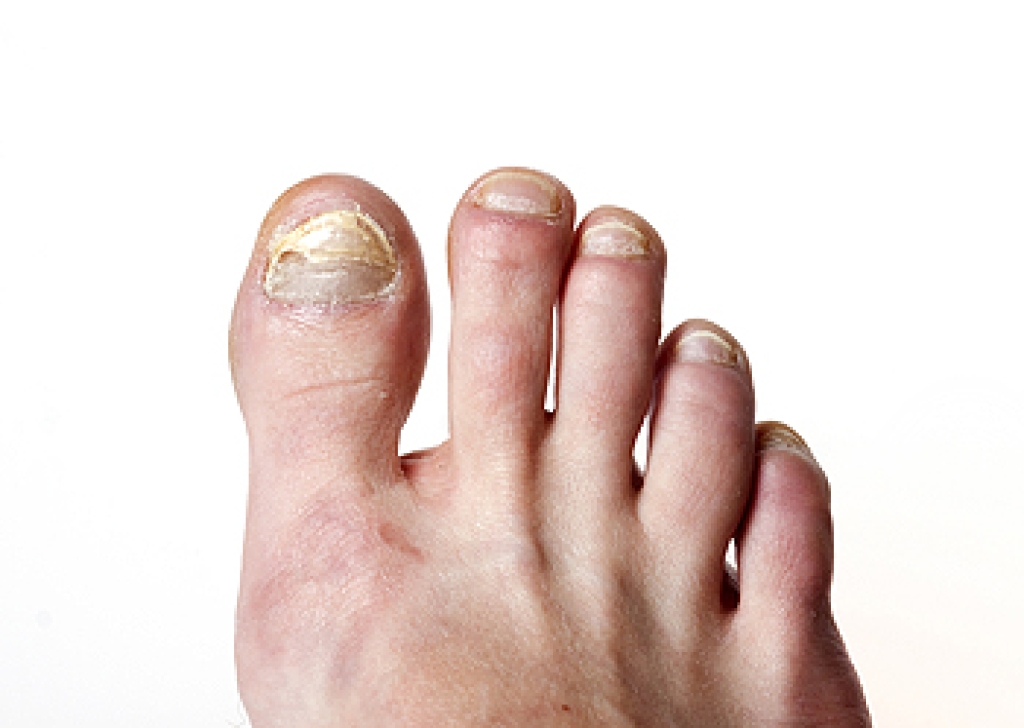

A common symptom of cuboid syndrome is pain along the outside of the foot which can be felt in the ankle and toes. This pain may create walking difficulties and may cause those with the condition to walk with a limp.